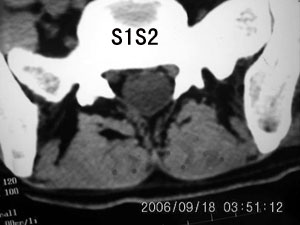

以下是引用守望可可西里在2006-9-18 21:29:00的发言:[br][br] 马尾肿瘤,密度较低,大部分似乎呈囊性变(看着很费眼),考虑室管膜瘤,建议mri。

以下是引用dyg在2006-9-18 22:27:00的发言:[br]正常脊髓.[br]分析:人的脊髓从枕大孔开始至腰1.2椎体为止,有2个生理膨大,分为颈膨大和腰膨大;该病人脊髓须然从腰段开始直至马尾似乎膨大,胆是与上段脊髓密度没有多大变化,所以我认为是正常膨大之延续;当然最好做ct增强或mri检查,排除肿瘤.

以下是引用飞虎在2006-9-18 20:18:00的发言:[br]部分椎管内密度不均且无ct值 故mri检查